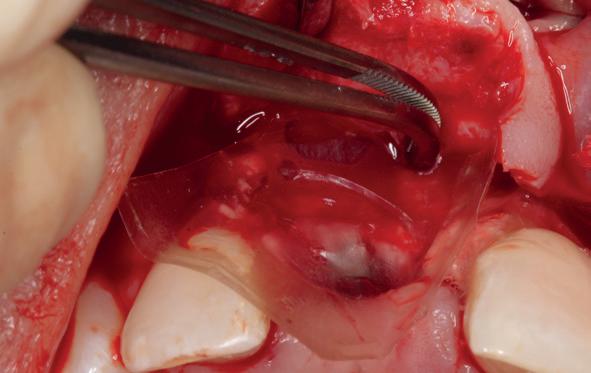

Lateraal van de implantaten wordt de kaak fors uitgebouwd volgens de Hybride GBR-techniek met Oragraft (allograft) van Lifenet die wordt vermengd tot een cocktail met BioOss (xenograft) van Geistlich, autoloog geoogste botsnippers en verzameld bloed uit het wondgebied. De botgraft wordt bedekt met een Ossix (crossed linked) membraan en met Hyadent (hyaluronzuur) overspoten. De sinuslift wordt gelijktijdig met de laterale botopbouw volgens de Caldwell Luc methode uitgevoerd en de uitgeprepareerde holte opgevuld met de botgraft. De flaps worden eerst horizontaal ontlast (gemobiliseerd) en vervolgens naar elkaar toe gehecht met vicryl rapide. Daarbij wordt gebruikgemaakt van horizontale matrassen, zodat de wondranden passief tegen elkaar

komen te liggen en de flaps primair gesloten kunnen worden. Het passief sluiten van een flap voorkomt wonddehiscenties in de genezingsfase die als complicaties kunnen optreden en botregeneratie verstoren. Daarnaast wordt bij een wonddehiscentie het risico op infectie van de graft sterk verhoogd waardoor het gewenste resultaat niet kan worden bereikt. Afstoting van graft materiaal komt dan veelvuldig voor soms gecombineerd met abcesvorming als geen voorzorgsmaatregelen worden genomen. Complicaties moeten daarom nauwlettend gevolgd worden totdat ze verdwenen zijn. De patiënt krijgt na chirurgie postoperatieve instructies en adviezen over de postoperatieve zorg. Daarbij wordt ook de nadruk gelegd op het koelen (coldpack) en zijdelingse druk op de wang. Het blijkt dat koelen en het uitoefenen van druk op het operatiegebied oedeem en hematoomvorming grotendeels kunnen verminderen en soms zelfs kunnen voorkomen.

Voor voorspelbare GBR wordt vaak het PASS-principe aangehaald: (P) primaire, spanningsvrije wondsluiting; (A) angiogenese en adequate perfusie; (S) space maintenance/creation; en (S) stabiliteit van het bloedstolsel en het graftcomplex.2 In de kliniek betekent dit dat flapdesign, periostale releasing incisions, fixatie van membraan/graft en hechttechniek net zo bepalend zijn als de keuze van het botvervangend materiaal.

Barrière-membranen variëren van resorbeerbare (meestal collageen) membranen tot niet-resorbeerbare barrières (PTFE of titaniumversterkte meshes). Resorbeerbare membranen zijn klinisch gebruiksvriendelijk waarbij een tweede ingreep kan vermeden worden om het membraan te verwijderen. Niet-resorbeerbare membranen bieden een hogere stabiliteit bij grotere botaugmentaties, maar zijn gevoeliger voor complicaties bij wonddehiscenties (perforaties) en vragen een strikt weke delenmanagement. Wonddehiscentie en membraanexpositie zijn de meestvoorkomende complicaties bij GBR en hebben aantoonbaar een negatief effect op botregeneratie. In een systematic review en meta-analyse was horizontale bottoename bij edentate botcresta aanzienlijk groter wanneer geen expositie optrad; ook reductie van peri-implantaire dehiscentiedefecten was beter zonder expositie.3 Daarmee wordt het belang onderstreept van passieve flapsluiting, drukvrij prothesegebruik en een actieve follow-up in de vroege genezingsfase.